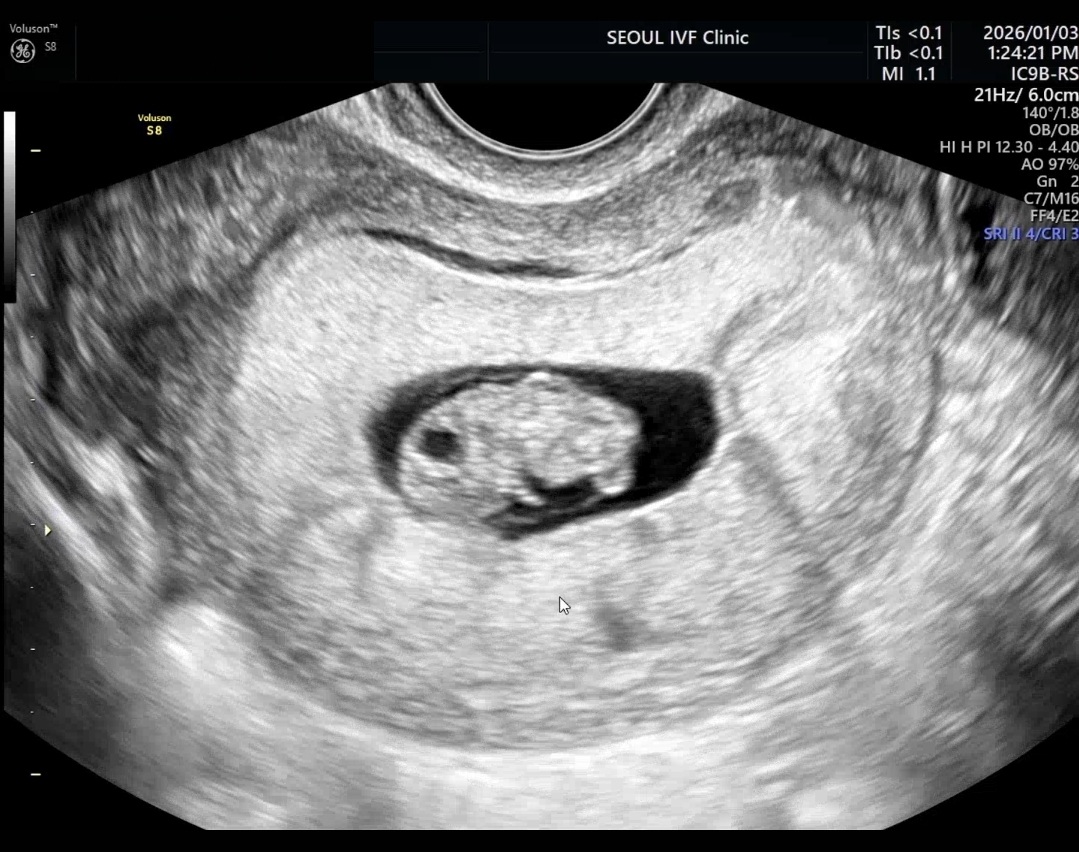

| 가슴 떨리는 임신 이야기를 공유해 주세요. | 1년 동안 자연임신을 시도했지만 쉽지 않았고, 세 번의 인공수정을 거친 끝에 긴 고민 후 시험관 시술을 결정했습니다. 배아 이식 후 결과를 기다리는 매일은 설렘과 불안이 교차하는 시간이었습니다. 임신이 확인되던 날, 작은 생명이 제게 와주었다는 사실에 가슴이 떨리고 눈물이 났습니다. 그날의 감정을 오래 기억하고 싶습니다. |

| 치료 도중 느꼈던 가장 기뻤던 순간과 절망적인 것들은 무엇인가요? 잊지 못할 경험이 있나요? | 가장 기뻤던 순간은 시험관 시술 후 임신이 확인되었을 때였습니다. 여러 번의 기다림과 걱정을 지나, 제 안에 새로운 생명이 자리 잡았다는 사실을 받아들이는 순간 마음이 조용히 벅차올랐습니다. 가장 절망적으로 느껴졌던 때는 1년간의 자연임신 시도와 세 차례의 인공수정이 모두 원하는 결과로 이어지지 않았을 때였습니다. 아무리 애써도 결과를 장담할 수 없다는 현실이 막막했지만, 그 시간을 견뎌낸 끝에 지금의 이 순간을 맞이할 수 있어 더욱 감사하게 느껴집니다. |